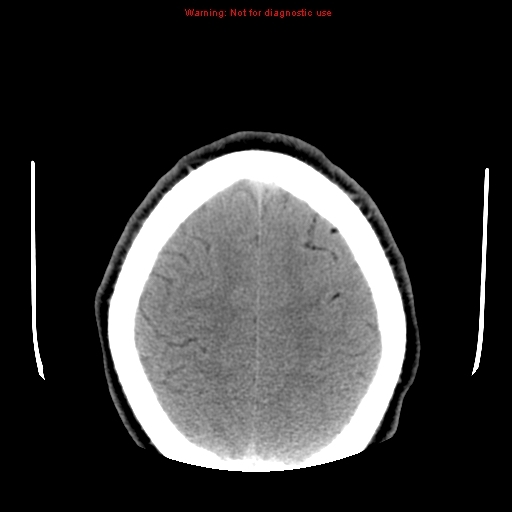

Cerebral fat embolism

Note the multiple sites of oedema and haemorrhage, involving the brain stem and corpus callosum as well as subcortical white matter and left cerebral peduncle. High FLAIR signal is also seen in the dorsal midbrain. EVD insitu.

Case Discussion

Diffuse axonal injury can be subtle on CT but have devastating consequences for the patient. This is a case of grade III injury (involvement of brainstem) and carries a poor prognosis.

Diffuse axonal injury

Diffuse axonal injury (DAI), also known as traumatic axonal injury (TAI), is a severe form of traumatic brain injury due to shearing forces. It is a potentially difficult diagnosis to make on imaging alone, especially on CT as the finding can be subtle, however, it has the potential to result in severe neurological impairment.

The diagnosis is best made on MRI where it is characterised by several small regions of susceptibility artifact at the grey-white matter junction, in the corpus callosum, and in more severe cases in the brainstem, surrounded by FLAIR hyperintensity.

Diffuse axonal injury is characterised by multiple focal lesions with a characteristic distribution: typically located at the grey-white matter junction, in the corpus callosum and in more severe cases in the brainstem (see: grading of diffuse axonal injury).

CT

Non-contrast CT of the brain is routine in patients presenting with head injuries. Unfortunately, it is not sensitive to subtle diffuse axonal injury and as such, some patients with relatively normal CT scans may have significant unexplained neurological deficit 4,5.

The appearance depends on whether or not the lesions are overtly haemorrhagic. Haemorrhagic lesions will be hyperdense and range in size from a few millimetres to a few centimetres in diameter. Non-haemorrhagic lesions are hypodense. They typically become more evident over the first few days as oedema develops around them. They may be associated with significant and disproportionate cerebral swelling.

CT is particularly insensitive to non-haemorrhagic lesions (as defined by CT) only able to detect 19% of such lesions, compared to 92% using T2 weighted imaging 4. When lesions are haemorrhagic, and especially when they are large, then CT is quite sensitive. As such, it is usually a safe assumption that if a couple of small haemorrhagic lesions are visible on CT, the degree of damage is much greater.